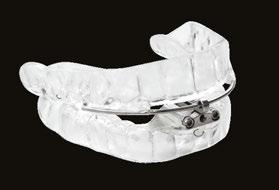

ances with precision tolerances as tight as 1/100th of a millimeter. This digital revolution required a billing code that could evolve alongside technological advancements, and CMS agreed that the Slow Wave’s DS8 was ideal for launching the new K1027 billing code. Where the industry had failed to create change, a single product introduction succeeded. The product definition of K1027:

“Oral device/appliance used to reduce upper airway collapsibility, without fixed mechanical hinge, custom fabricated, includes fitting and adjustment.”

This more inclusive product definition has resulted in more than 27 products being approved under the new billing code in the three years since it was established by CMS.5

In 2017, the first oral appliance was dual cleared for OSA/Bruxism by the FDA. The LUCO Hybrid was initially cleared for bruxism in 2015 [510(k) # K16047] and, based on clinical data, cleared for OSA in 2017 [510(k) # K130797]. However, no one understood the implications of what this could do for the dental industry. In July 2024, the FDA dual cleared the Slow Wave DS8 for the treatment of OSA/Bruxism K191320 and K240463. The product, now marketed as BROSA (Bruxism, Retainer, OSA), is prescribed by dentists for a bruxism condition that shares a significant overlap with OSA.

Now, dentists can prescribe a product to treat a patient’s bruxism in just one visit and have treatment within days. The patient can also simultaneously monitor its impact on their sleep patterns. This new model makes it profitable for the dentist to make OAT a mainstream product.

But what makes devices like BROSA effective for both OSA and bruxism? Two key factors are the vertical opening of the mandible and making more room for the tongue.

Traditional devices advance the mandible forward in millimeter increments to open the airway. Still, research has shown that incorporating more vertical opening and making more room for the tongue allows for less forward movement of the mandible. This can reduce or eliminate the need for a morning repositioner, as the jaw remains in a more relaxed state during sleep. This relaxed state is not only beneficial for OSA but also ideal for treating bruxism.

The Slow Wave BROSA device further enhances this relaxation thanks to how well the Formlabs material glides while using a ramp system that allows for a very smooth natural horizontal movement during sleep. The innovative ramp mechanism ensures that the more a patient bites down, the more the ramps gently advance the mandible forward. This system allows the body to find its ideal jaw position naturally during sleep. Initial use of the BROSA device in patients enabled 24 of 25 to achieve normal breathing levels of fewer than 5 AHI events per hour. These outcomes were observed across patients with mild, moderate, and severe OSA.